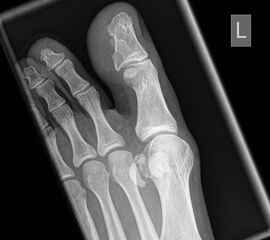

Sprunggelenk Mortise Aufnahme ohne Belastung (Mortise-View)

Positionierung:

• Zur Abbildung der Sprunggelenkgabel wird der Fuß 20° innenrotiert, um eine exakte ap-Abbildung der Malleolengabel zu erreichen.

• In dieser Aufnahme wird der mediale und laterale Gelenkspalt des Talus mit identischer Breite abgebildet.

• Innen- und Außenknöchel befinden sich in gleicher Distanz zum Röntgenfilm.

• Zentralstrahl wird mittig auf den Gelenkspalt am oberen Sprunggelenk zentriert.

Kennzeichen des Röntgenbildes:

• Darstellung des Talusdoms ohne Überlagerung.

• Das Sprunggelenk befindet sich dabei in 90° Stellung, um eine Überlappung des Kalkaneus mit der distalen Fibula zu vermeiden.

• Der Weichteilmantel ist erkennbar.

Besondere Bemerkungen zum Beispielbild:

• Die Innenknöchelfraktur ist deutlich besser nachvollziehbar als bei der ap Aufnahme (siehe vorheriges Bild).

• Keine Stufe im Gelenk.

• Die Wachstumsfugen sind noch erkennbar, im Wesentlichen aber geschlossen.